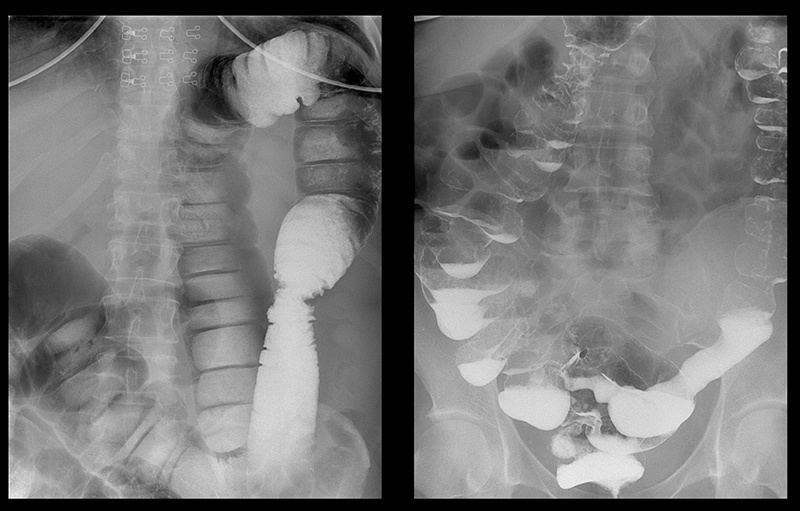

Подивіться знімки органів людей, у яких усе почалося з неприємного запаху з рота, запорів та печії, а закінчилося доповіддю патологоанатома.

‘’Рак товстої кишки у жінки зі скаргою на часті запори’’

‘’Рентгенографія калового каміння в товстій кишці’’

‘’Стадії раку прямої кишки які формуються протягом 1-2 років’’